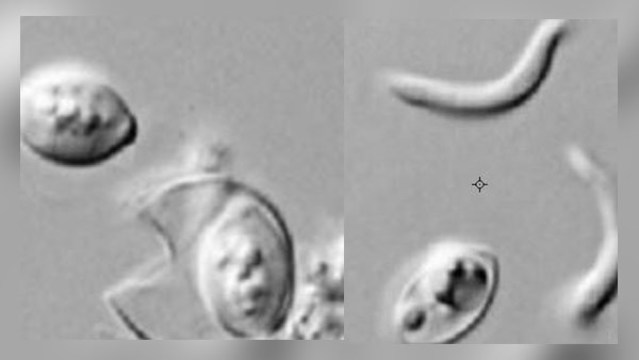

El Servicio de Inspección y Seguridad de Alimentos en el Departamento de Agricultura indicó que el parásito en cuestión es conocido como cyclospora, el cual genera dolor intestinal, diarrea, náuseas, vómitos, fatiga, perdida de peso y en algunos casos fiebre o escalofríos.